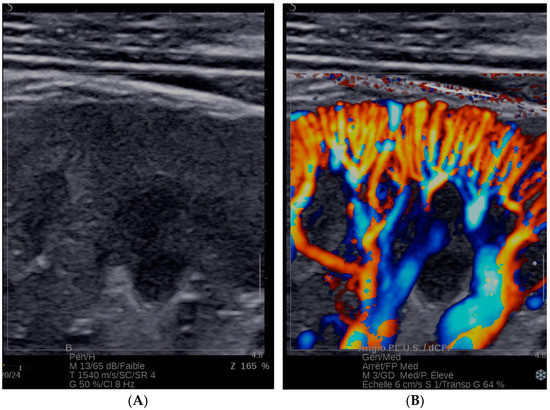

- Bardin, T.; Nguyen, Q.D.; Tran, K.M.; Le, N.H.; Do, M.D.; Richette, P.; Letavernier, E.; Correas, J.-M.; Resche-Rigon, M. A cross- sectional study of 502 patients found a diffuse hyperechoic kidney medulla pattern in patients with sereve gout. Kidney Int. 2021, 99, 218–226. [Google Scholar] [CrossRef]

- Rahmouni, A.; Bargoin, R.; Herment, A.; Bargoin, N.; Vasile, N. Color Doppler twinkling artifact in hyperechoic regions. Radiology 1996, 199, 269–271. [Google Scholar] [CrossRef] [PubMed]

- Bardin, T.; Tran, K.M.; Nguyen, Q.D.; Sarfati, M.; Richette, P.; Vo, N.T.; Bousson, V.; Correas, J.-M. Renal medulla in severe gout: Typical findings on ultrasonography and dual-energy CT study in two patients. Ann. Rheum. Dis. 2018, 78, 433–434. [Google Scholar] [CrossRef]